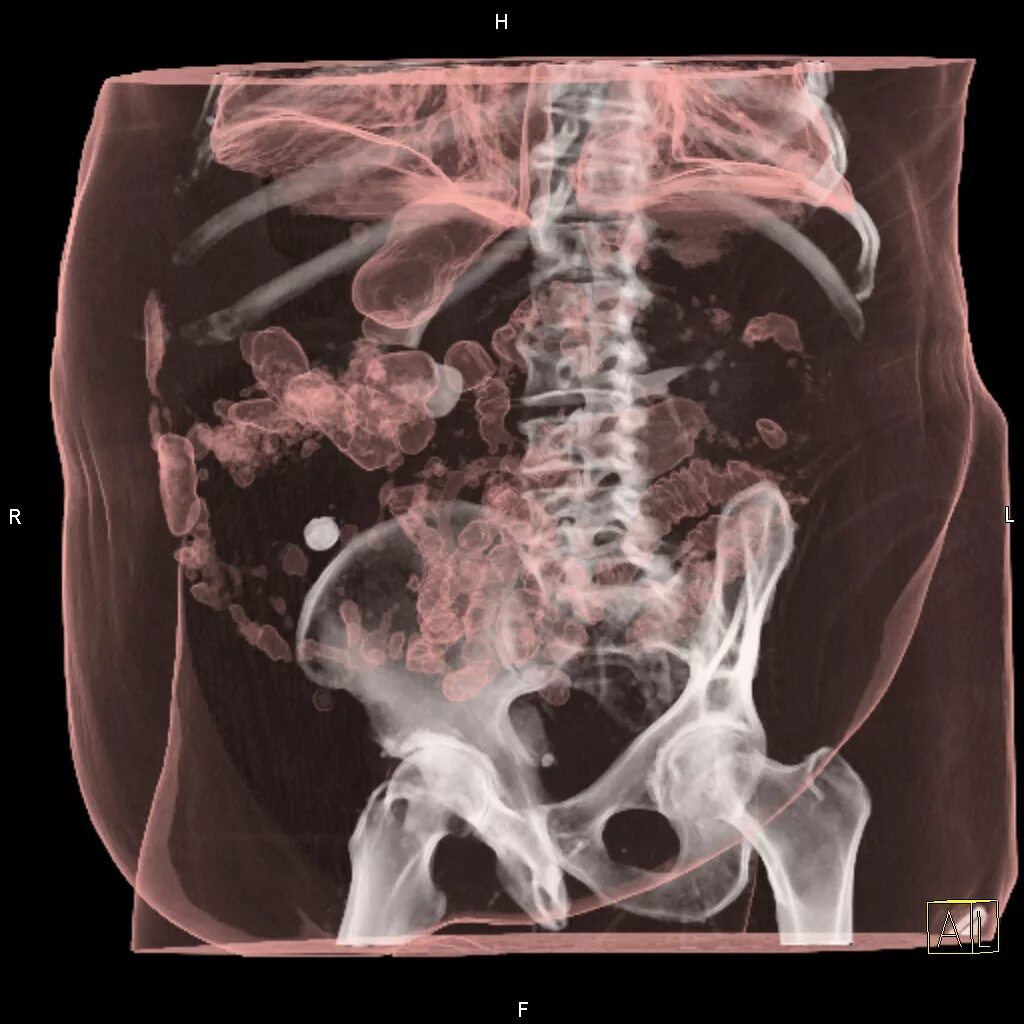

Мрт обп с контрастированием